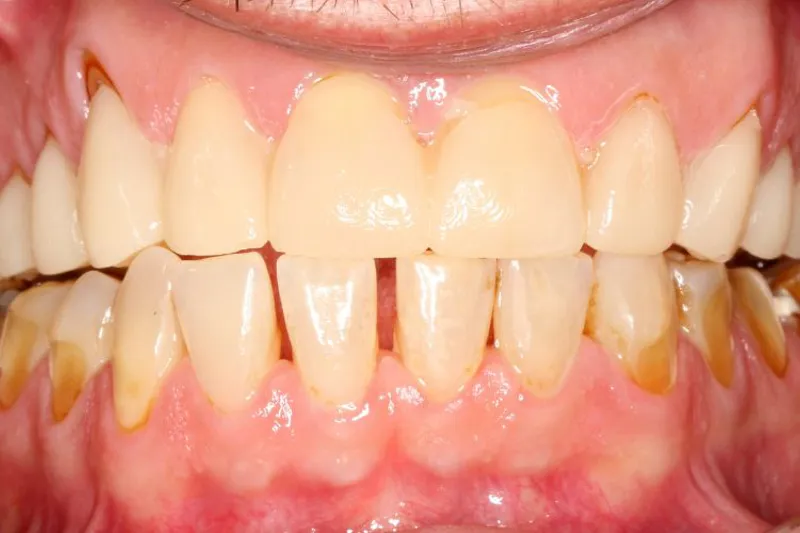

Det aktuelle patienttilfælde beskriver rehabiliteringen af en 45-årig mand med et erosionsskadet tandsæt. Patienten ønskede æstetisk forbedring samt en forudsigelig rehabilitering. Der blev benyttet en digital arbejdsgang for at sikre det æstetiske resultat samt bistå tandlægen i de kliniske procedurer. Den initiale digitale planlægning (mockup) blev præsenteret for patienten intraoralt. Efter at patienten havde godkendt planen, blev der foretaget en ortodontisk behandling med ”clear alignere”. Der blev udført kvantificerede præparationer gennem den intraorale mockup. Mockup og præparationer blev overført til tandteknikeren ved hjælp af intraoral scanner. Der blev efter den oprindelige plan fremstillet fuldkonturerede keramiske erstatninger – som derefter blev cementeret med en adhæsiv protokol.

The current patient case describes the rehabilitation of a 45-year-old man with a severe dental erosion. The patient desired aesthetic improvement as well as predictable dental rehabilitation. A digital workflow was used to ensure the aesthetic result and assist the dentist in the clinical protocols. The initial digital planning (mock-up) was presented to the patient intraorally. After the patient approved the plan, orthodontic treatment based on “clear aligners” was carried out. Quantified preparations were performed through the intraoral mockup according to the requirements of the ceramic material. An intraoral scanner was used to transfer the mockup and preparations to the dental technician in one digital file. Full-contour ceramic replacements were manufactured according to the original plan – which were later luted using an adhesive protocol.